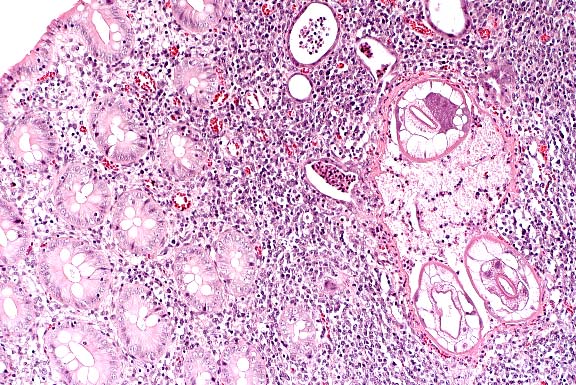

- Case 12-1. Liver. Acute necrosis with intact parenchyma.

10X

- AFIP Diagnoses:

- 1. Liver: Hepatitis, necrotizing, acute, periportal to midzonal,

diffuse, moderate, rabbit, lagomorph.

- 2. Lung: Fibrin thrombi, multifocal, with mild acute interstitial

pneumonia.

- 3. Lung, blood vessels: Medial hypertrophy, multifocal, moderate.

- 4. Spleen: Congestion, hemorrhage, and fibrin deposition,

acute, diffuse, severe, with lymphoid necrosis.

- This case is typical for the disease in susceptible adult

rabbits, and is almost uniformly fatal. Many animals are found

dead without premonitory signs, and those found alive rapidly

become comatose and die quietly. Blood-stained frothy fluid may

exude from external nares, and the lungs are edematous. Typically,

there is complete destruction of the sinusoidal architecture

of the liver and spleen, and replacement by fibrinous coagulum

containing erythrocytes. Destruction of white pulp may occur

as in this case, but is not uniformly present and may be secondary

to stress rather than a direct effect. Acute coagulation necrosis

in the liver is typically periportal, extending to midzonal areas

as in this case, and is usually accompanied by a minimal inflammatory

response.